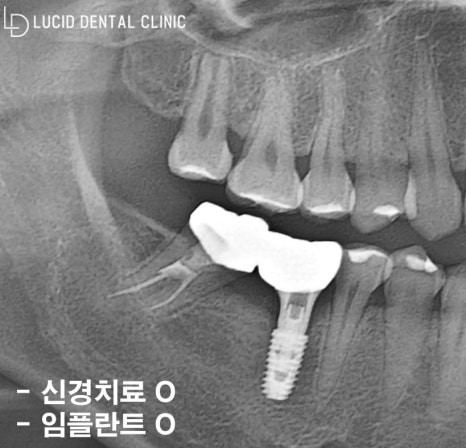

위와 같은 치료 과정을 거치며

약 3개월의 회복 시간을 보냈는데요

실제로 환자께서 정기 검진도 꾸준히 받아주시고,

관리도 꼼꼼히 시행해 주셔서 굉장히 빠른 속도로

회복하는 모습을 확인할 수 있었습니다.

이렇게 제작한 최종 보철을 체결해 드리며

계획한 치료 과정을 모두 마칠 수 있었습니다.